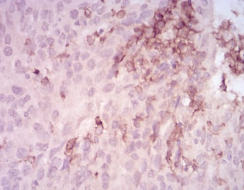

MMP14 Mouse Monoclonal antibody[61D1]

Proteins of the matrix metalloproteinase (MMP) family are involved in the breakdown of extracellular matrix in normal physiological processes, such as embryonic development, reproduction, and tissue remodeling, as well as in disease processes, such as arthritis and metastasis. Most MMP's are secreted as inactive proproteins which are activated when cleaved by extracellular proteinases. However, the protein encoded by this gene is a member of the membrane-type MMP (MT-MMP) subfamily; each member of this subfamily contains a potential transmembrane domain suggesting that these proteins are expressed at the cell surface rather than secreted. This protein activates MMP2 protein, and this activity may be involved in tumor invasion.

Immunogen:    Purified recombinant fragment of human MMP14 (AA: 112-246) expressed in E. Coli.

IHC    1/200 - 1/1000